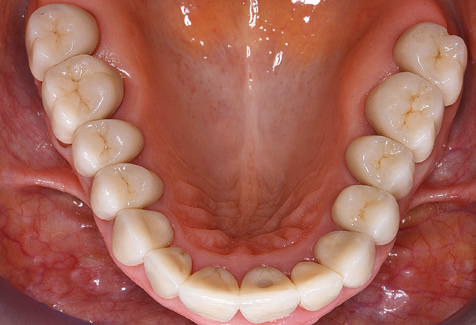

Fig. 9: The accessible implant and tooth surfaces are polished with polishing cups and suitable polishing compounds. – Fig. 10: Repeat instruction in the use of appropriate aids for oral hygiene at home should also form part of SPT. – Fig. 11a and b: Clinical situation 12 years after insertion of the prosthetic restoration. During this period, only a veneering ceramic fracture on tooth 47 and the requirement for endodontic treatment of tooth 12 were observed. All restorations are still functioning as intended.

Summary

Standardised and regular risk-adapted care in the scope of SPT is the key to treatment success for the clinical long-term success in periodontically compromised patients. This is particularly true for patients fitted with implants following successfully completed periodontal treatment (Fig. 11a and b).